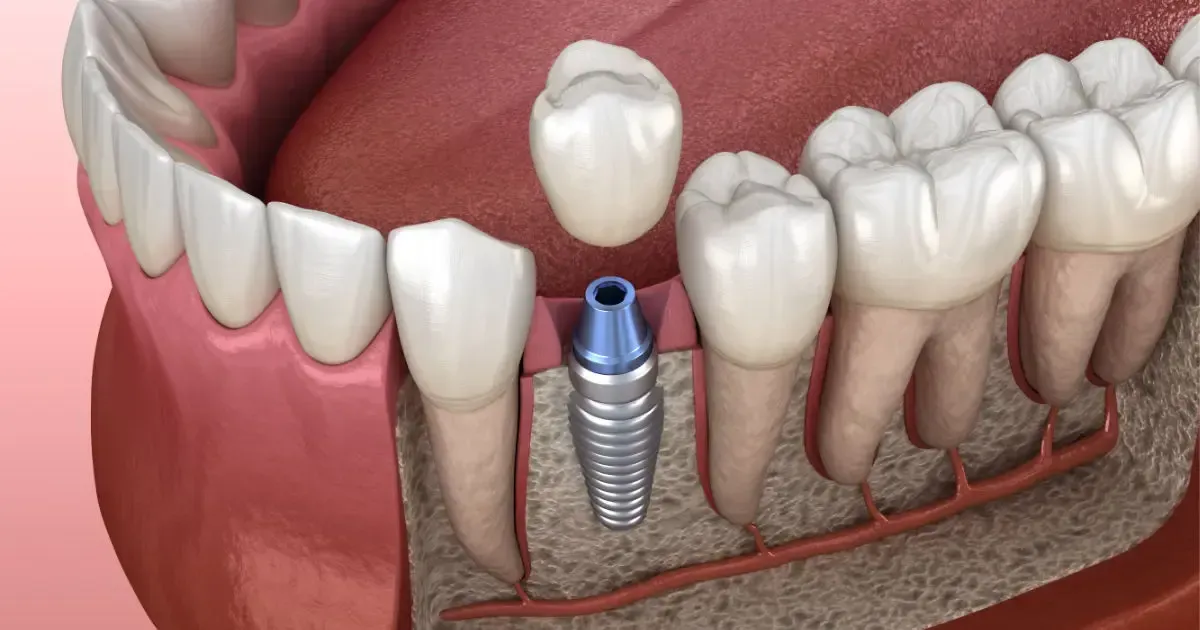

Implantes de gama internacional

Marcas con respaldo científico y estudios clínicos a largo plazo.